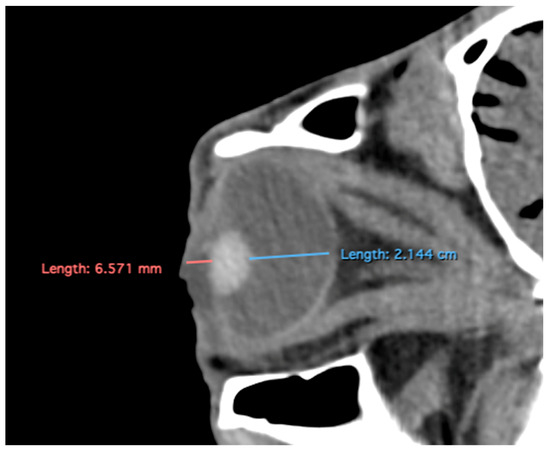

Figure 4.

Parasagittal multiplanar reconstruction (MPR) images of the equine eyeball showing (A) eyeball length and (B) the maximal antero-posterior distance of the lens measured along its midline.

- Lens rostrocaudal length: Maximum anteroposterior distance of the lens measured along its midline (Figure 4B).

Table 1 provides summary statistics (mean, median, range, and standard deviation) for the internal ocular measurements of the left eye, right eye, and both eyes combined across all 20 horses. The average ocular measurements indicated that the eyeball height (5.19 ± 0.13 cm) was greater than its width (4.28 ± 0.12 cm), confirming the characteristic oval shape of the equine eye. The mean axial length was 5.09 ± 0.17 cm, consistent with previous descriptions of large-globe morphology in horses. The orbital cavity measured 5.27 ± 0.12 cm in height and 6.29 ± 0.14 cm in length. The anterior and posterior chambers had mean widths of 0.56 ± 0.07 cm and 2.26 ± 0.09 cm, respectively. The lens exhibited a mean height of 1.53 ± 0.06 cm, width of 1.23 ± 0.06 cm, and length of 1.63 ± 0.04 cm. These results collectively reflect the regular proportions and bilateral symmetry of the equine eyeball and its internal structures, as detailed in Table 1. The Mann–Whitney U test revealed no statistically significant differences in the measurements between the right and left eyes. Similarly, when all variables were considered collectively, the analysis confirmed the absence of significant differences between both eyes